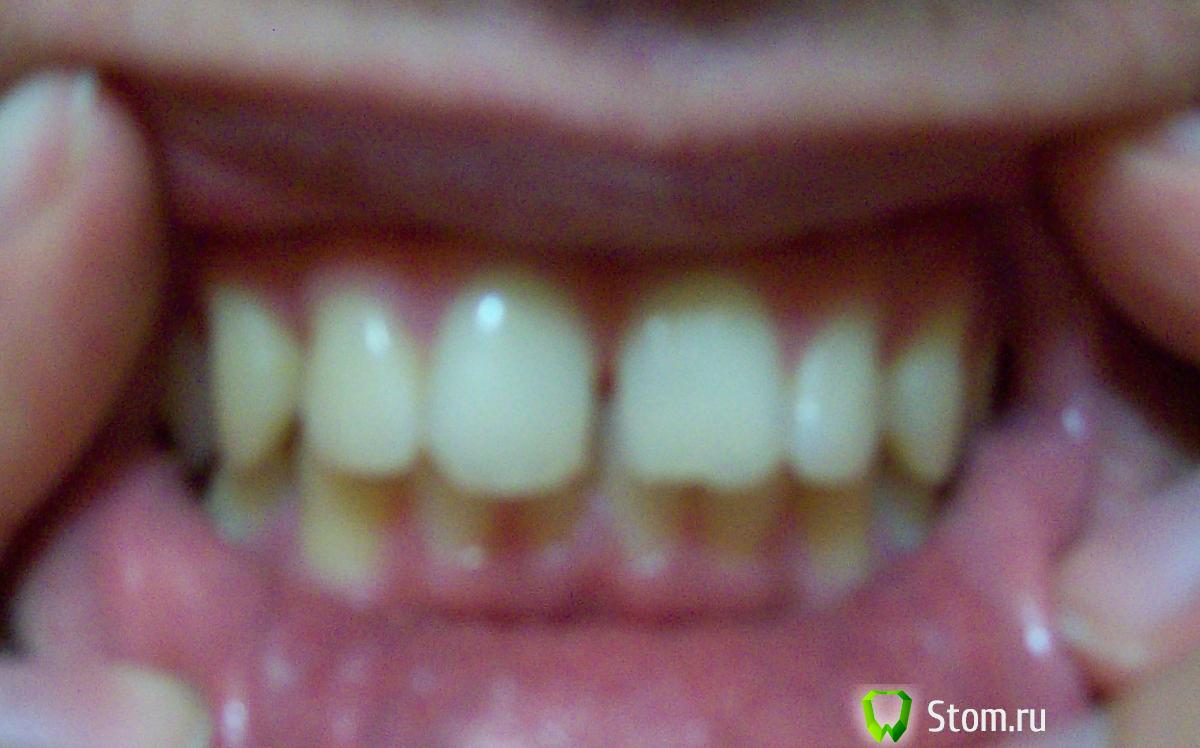

Здравсвуйте. Мне 23 года. Наконец-то руки добрались до кривых зубов. Цель была выпрямить зубы, убрать тремы, ну и заодно выпрямить прикус. Ортодонт на приеме сказал, что прикус у меня ужасный, что из-за него у меня впоследствии (лет через 10) будут большие проблемы с парадонтом, которые уже начались сейчас судя по снимку. Теперь меня забеспокила уже другая проблема. Два центральных нижних зуба у меня действительно немного шатаются уже сейчас. Действительно ли у меня настолько ужасный прикус, что из-за него через несколько лет зубы начнут еще больше шататься? Или же дело вовсе не в прикусе? И прокомментируйте пожалуйста парадонт на снимках тоже. Спасибо.

Основная нагрузка при функции приходится на фронтальные зубы, отюда подвижность и стираемость. Возможные проблемы с пародонтом могут быть связаны именно с неправильной нагрузкой. Правильное ортодонтическое лечение поможет решить вашу проблему, неправильное - ухудшит.